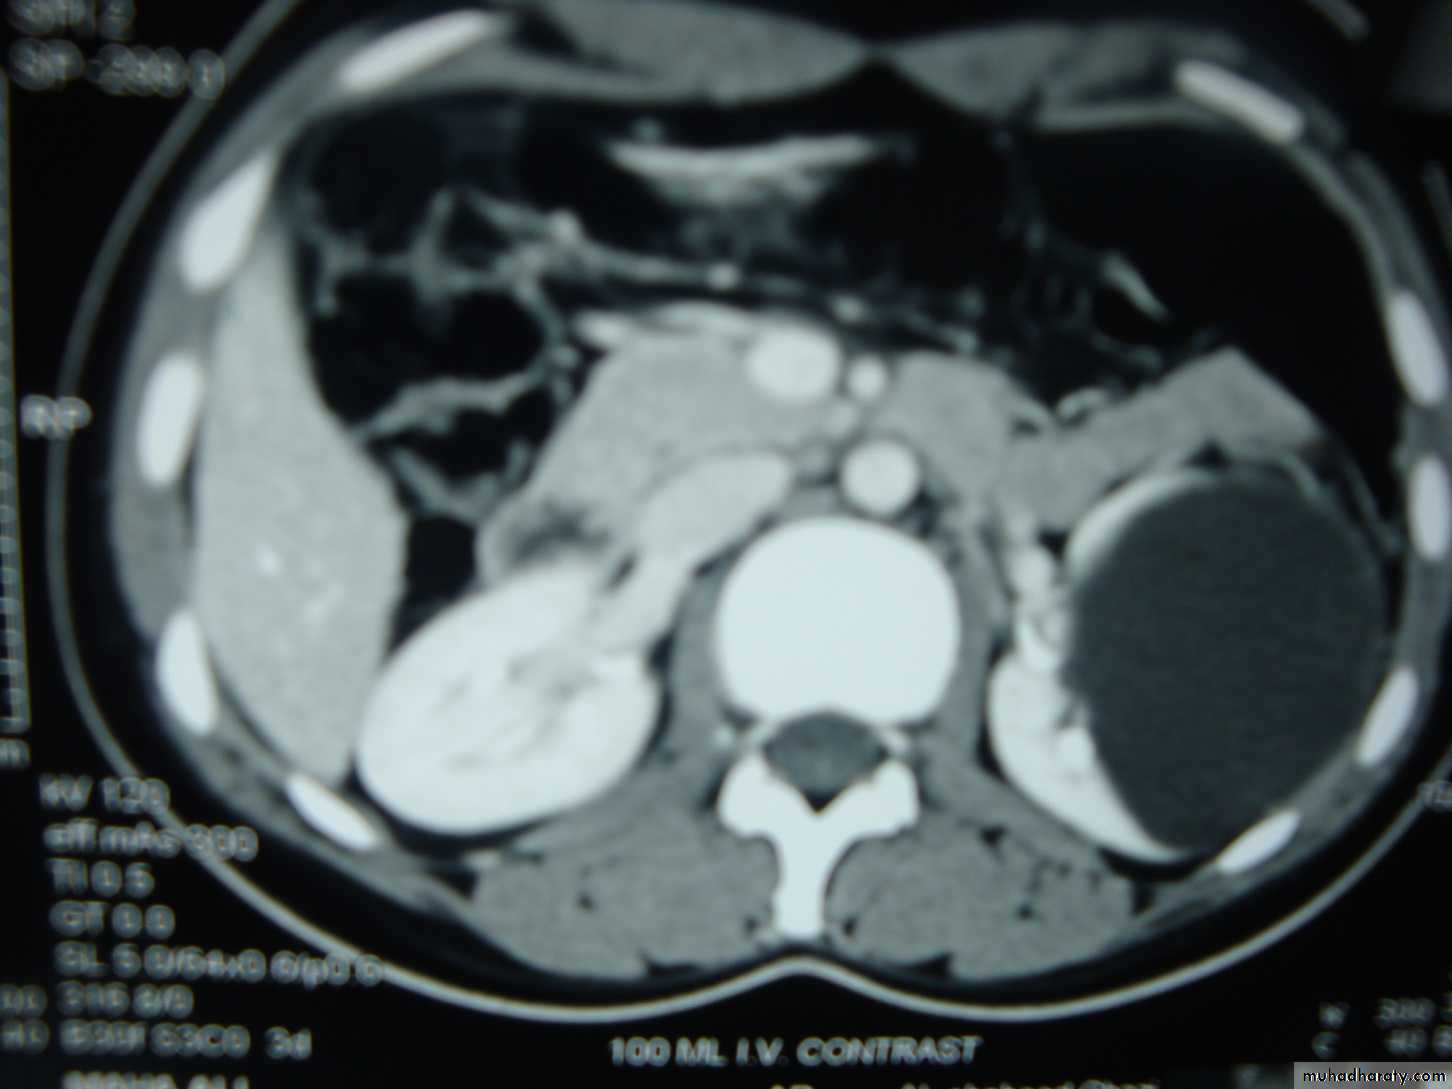

A 55-year-old man with hematuria , What's this study and abnormal finding ?

Ct enhanced

Renal cyst type 4 with calcification and peripheral enhancement needs radical nephrectomyBosniak's class II renal cysts. A, CT scan shows right renal cyst with thin internal septation.